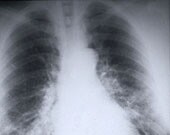

CT Scans for Lung Cancer Result in Few False-Positives

Concerns that wider adoption of the screen might lead to unnecessary surgeries are unfounded